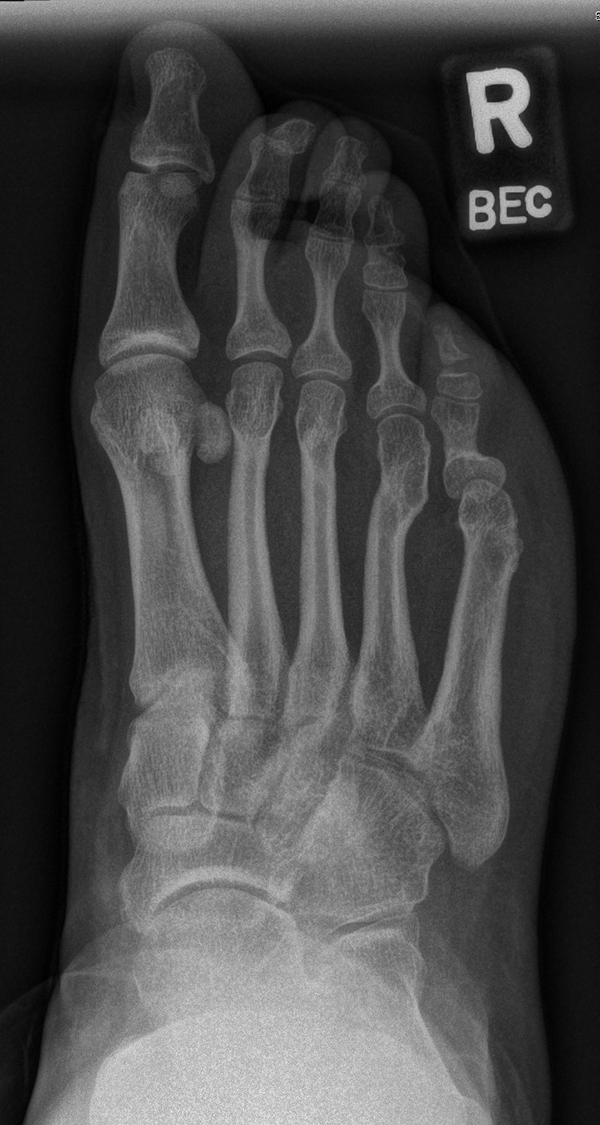

Abb. 28 a-g: Radiologischer Verlauf einer Chevronosteotomie nach dem Verfahren von M. Elkaim mit prä- (a-c drei unterschiedliche Ansichten) und intraoperativen Röntgenbildern in zwei Ansichten (d-e) sowie postoperativ zwei Ansichten (f-g).

Zum Lesen der Bildbeschreibung und zur Vollansicht bitte die Bilder anklicken. Bilder: A. Helmers.

Sie wird über eine eigene Tapetechnik fixiert und kann bei einem erhöhten Intermetatarsale-Winkel alternativ zur Scarf-Osteotomie durchgeführt werden. Nachteile der Methode sind eine deutliche Verkürzung durch die Fräse sowie eine starke Plantarisierung des Metatarsale I Köpfchens. Um die Verkürzung zu vermeiden, wird verlängernd in Richtung des Metatarsale II Köpfchens (nicht wie offen in Richtung Metatarsale IV Köpfchen) osteotomiert. Gleiches gilt für die starke Plantarisierung, die durch den Knochenverlust der Fräse entsteht. Die Korrektur eines kindlichen oder jugendlichen Hallux valgus ist mit der Methode ansonsten suffizient durchführbar. Wird verkürzt, muss ausreichend plantarisiert werden, um eine Transfer-Destabilisierung MT II-IV zu vermeiden.

Die MICA-Technik sollte bei geschlossenen Fugen mit einem weitem intermetatarsale Winkel durchgeführt werden. Die dafür typische Verschraubung der Osteotomie kann bei geschlossenen Fugen ohne Probleme erfolgen. Diese Osteotomie kann gut mit einer Akin- und den beschriebenen Kleinzehen-Osteotomien kombiniert werden.